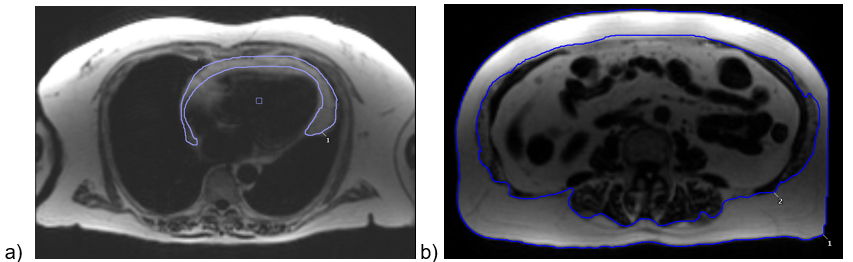

In addition to volumes, a fat/water separated multi-echo GRE sequence was acquired, and fat images manually contoured in cvi42 (Calgary, Canada). Areas of epicardial adiposity tissue (EAT) were averaged over 10 long-axis slices from the level of the great vessels to the true cardiac apex. Areas of abdominal subcutaneous (SAT) and visceral (VAT) adiposity tissue were averaged over 5 contiguous axial slices centred at L2-L3 intervertebral disc level.